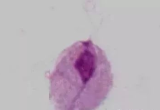

BV是细菌性阴道炎(bacterial vaginosis)的简称,它是加特纳菌和厌氧菌混合感染所导致的阴道内微生态平衡失调,10%~50%的患者...